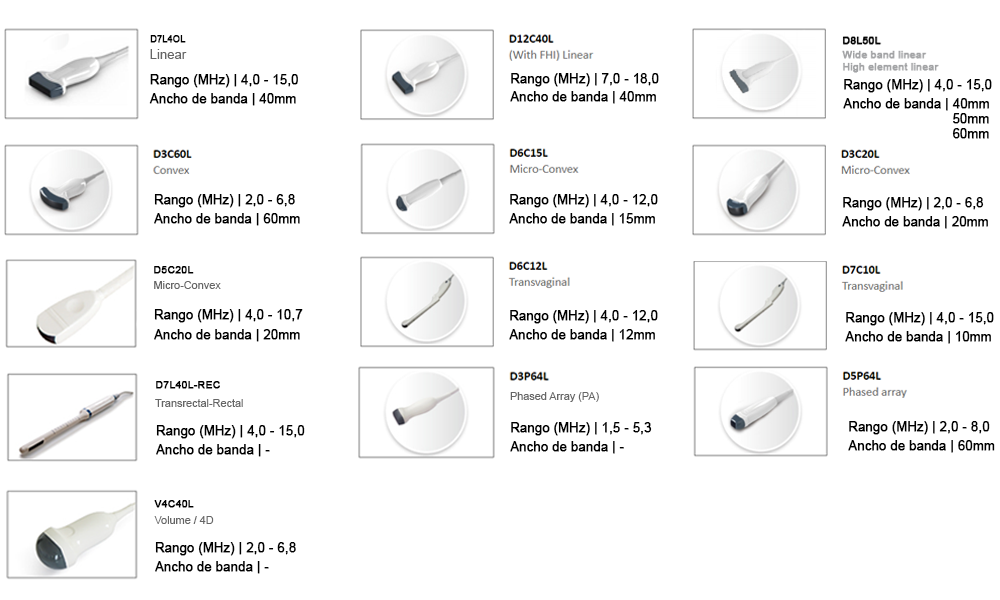

Choisissez la sonde pour équiper votre échographe CBit6